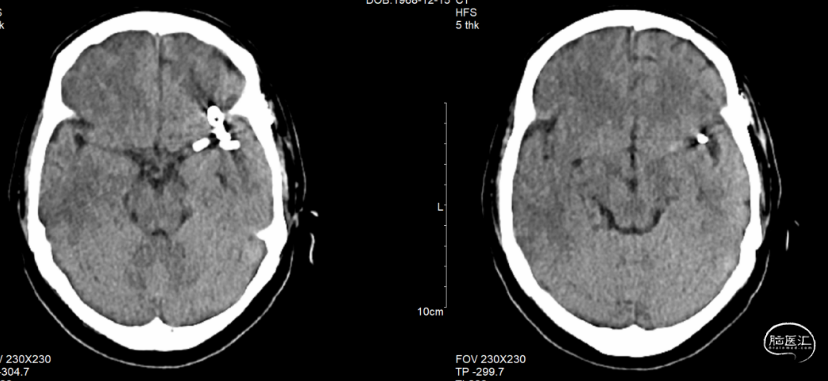

术后患者一般情况良好,无明显神经功能缺损。术后术后第1天复查头颅CT无明显脑出血及梗塞改变(图12),术后第2天顺利出院。术后予以双抗3月,长期阿司匹林单抗。术后3个月行颅脑MRA检查显示左侧大脑中动脉M1局部显影不佳(图13);术后7个月复查DSA提示左侧大脑中动脉M1段夹层动脉瘤较前明显缩小,支架无短缩(图14)。术后2年复查DSA见左侧大脑中动脉M1段夹层动脉瘤瘤体不显影,载瘤动脉及重要分支通畅(图15)。